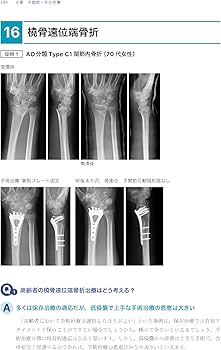

外傷整形外科に関する専門的な知識を深めるための書籍です。- 著者: 土田芳彦- タイトル: 考える外傷整形外科!- 出版社: 医学書院裁断済のため傷や汚れありとしていますが、明らかな汚れはなく、問題なくスキャンもできました。確認した範囲では書き込みやマーカーなどはありません。見落としありましたら申し訳ありません。よろしくお願い致します。